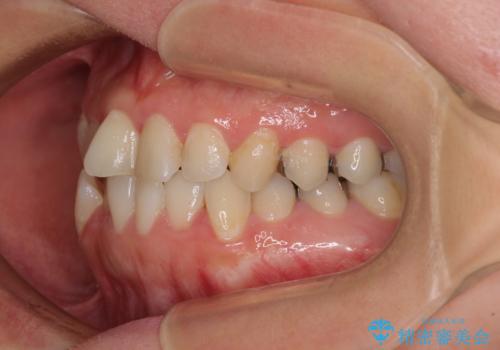

下顎犬歯のクロスバイトが認められ、インビザライン矯正ではクロスバイト改善に伴い奥歯が噛みにくくなることが予想されたため、上下顎間ゴムを積極的に使用して咬み合わせの安定を図ることとしました。

痛みなどの症状のあった歯は、矯正治療中の咬み合わせの変化により症状が強くなったため、一時的に咬合しないようにし、矯正治療後に症状がないことを確認して修復治療を行いました。